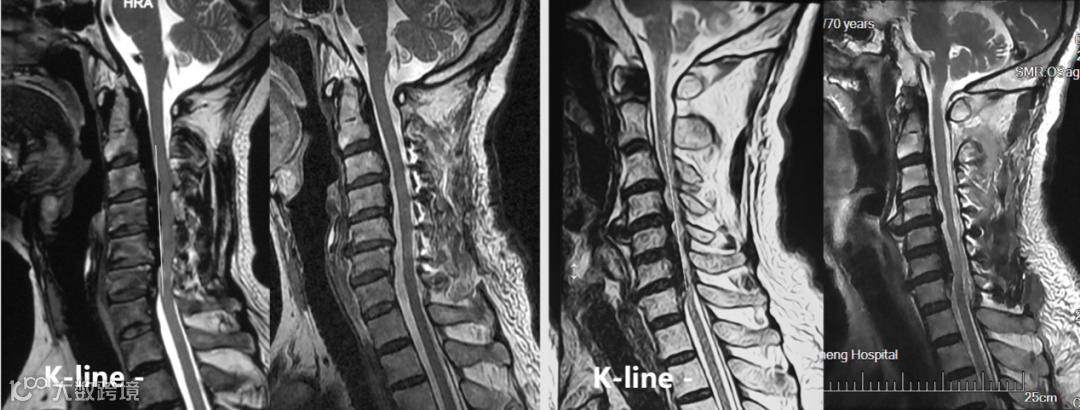

然而,有一小部分学者对K线提出了质疑,认为:K线不能预测单开门术后脊髓漂移情况、K线与神经功能恢复没有相关性[6]。

我们对大量的临床病例进行总结,发现K线存在诸多不足:K线仅适用于OPLL,且对OPLL累及上颈椎、上胸椎不适用;过于强调颈椎曲度在单开门手术中的作用;只承认单开门手术的间接减压作用,完全忽略了单开门手术的直接减压作用;认为脊髓漂移不充分就会导致神经功能将恢复不理想,二者存在必然的联系。

我们大量的临床病例证实:K线阴性的OPLL患者单开门术后脊髓漂移充分、神经功能恢复良好[7]。因此,我们认为:K线不具有预测脊髓漂移程度和神经功能恢复的作用。

上述病例证实:K线不能预测单开门术后脊髓漂移情况及神经功能的恢复情况;脊髓漂移程度与K线没有相关性;PCS评分具有预测神经功能恢复情况、指导手术方式选择、明确手术范围的作用。

③即使在K线的适用范围,其预测作用也很不准确,K线阴性的OPLL单开门术后脊髓也会获得充分漂移,此方面已有较多的文献报道。

④K线认为脊髓漂移不充分就会导致神经功能恢复不理想,完全将脊髓漂移程度和神经功能恢复程度混为一谈,事实上,脊髓漂移不充分只是神经功能恢复差的其中一个因素。

⑤K线过于强调颈椎曲度在单开门手术中的作用,我们大量的临床病例证实后凸不影响脊髓漂移程度,此方面也有类似的文献报道。

⑥K线只承认单开门手术的间接减压作用,K线认为脊髓漂移不充分就会导致神经功能将恢复不理想,片面地认为单开门手术只有脊髓向后漂移的间接减压作用,这完全忽略了单开门手术的直接减压作用[10, 11]。